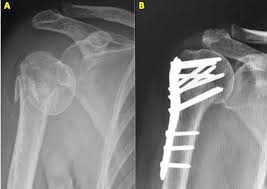

• Imaging such as X-rays, CT scans, or MRI to identify fractures, joint injuries, or soft-tissue damage.

When surgery is required, the goal is to realign, stabilise, and repair the injured structures. Common procedures include: